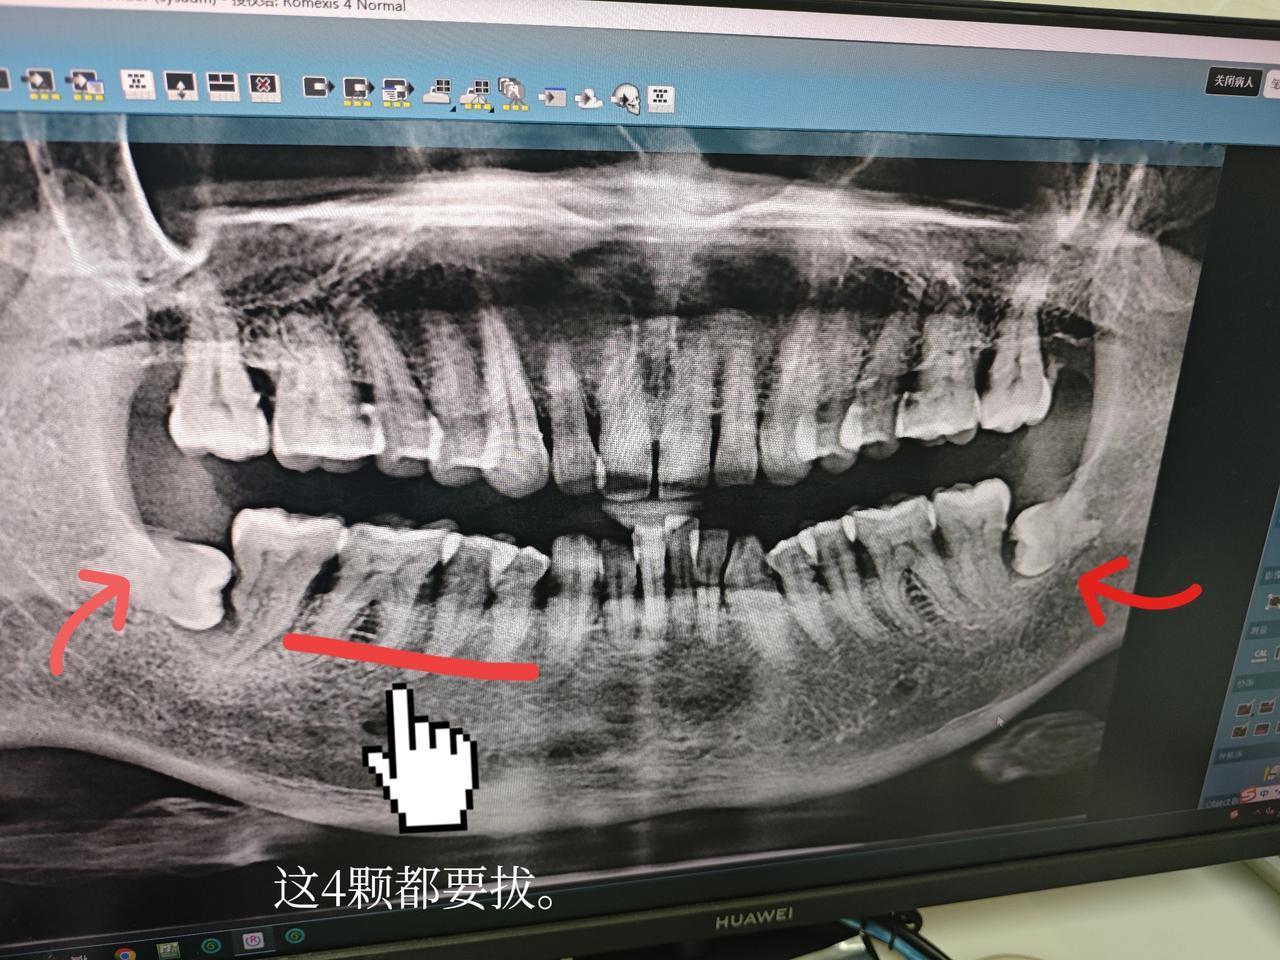

千万不要听医生的,牙齿一痛就去拔。 前段时间我因为牙齿痛,牙龈发炎,牙齿就松动了,痛的时候是真痛,就想把它拔来扔掉。 到三甲医院去检查,我明明只有一颗牙齿松了,也是那一颗痛,他却说挨着那4颗都要拔掉。光拔掉怎么行呢?拔掉了还要种啊,种一颗要4000多,我一算,4颗牙齿都要1万多,就心疼钱算了。 没想到的是,回来之后痛了几天,他就慢慢好了,到现在竟然一点都不痛了,能正常嚼东西,松的那颗好像也不怎么松了。 想想如果我当时听了医生的话,不光是人受罪,那个钱也受罪呀。 当然我这种情况应该也不是普遍的,有的人肯定也忍不了那个痛。因为痛的时候是真的痛,也是很烦的。 但道理很简单,牙齿痛多半是因为发炎,蛀牙除外,过了一阵就好了。我始终觉得一痛就拔,这个做法本身就不对,就好比我们的手指痛,不可能把手指剁掉吧。 我们本身就是有免疫力的。我们要相信自己的身体,免疫力是可以免疫一切的。